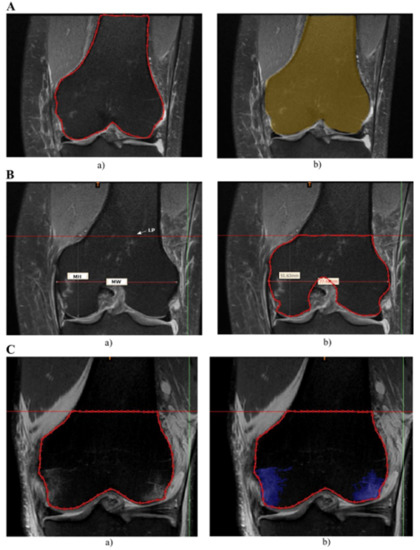

2.1. Measurements of Bone Bruises

2.2. Determining Total Bone Volume

2.3. Segmentation of BB

- in femur:

- in tibia:

2.4. Measurement of Bone Tunnel

- percentage increase in tunnel diameter in the femur and tibia:where Δfd—is an increase in the femur, —is an increase in the tibia, dp—is an initial tunnel’s diameter, di—is a value of the tunnel’s diameter in a specific part of the tunnel, and n—is a sample size.

- percentage increase in tunnel area in the femur and tibia:where —is an increase in the femur, —is an increase in the tibia, CSAp—is an initial tunnel’s area, CSAi—is a value of the tunnel’s area in a specific part of tunnel, and n—is a sample size.